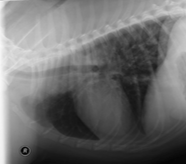

Diagnostic Imaging